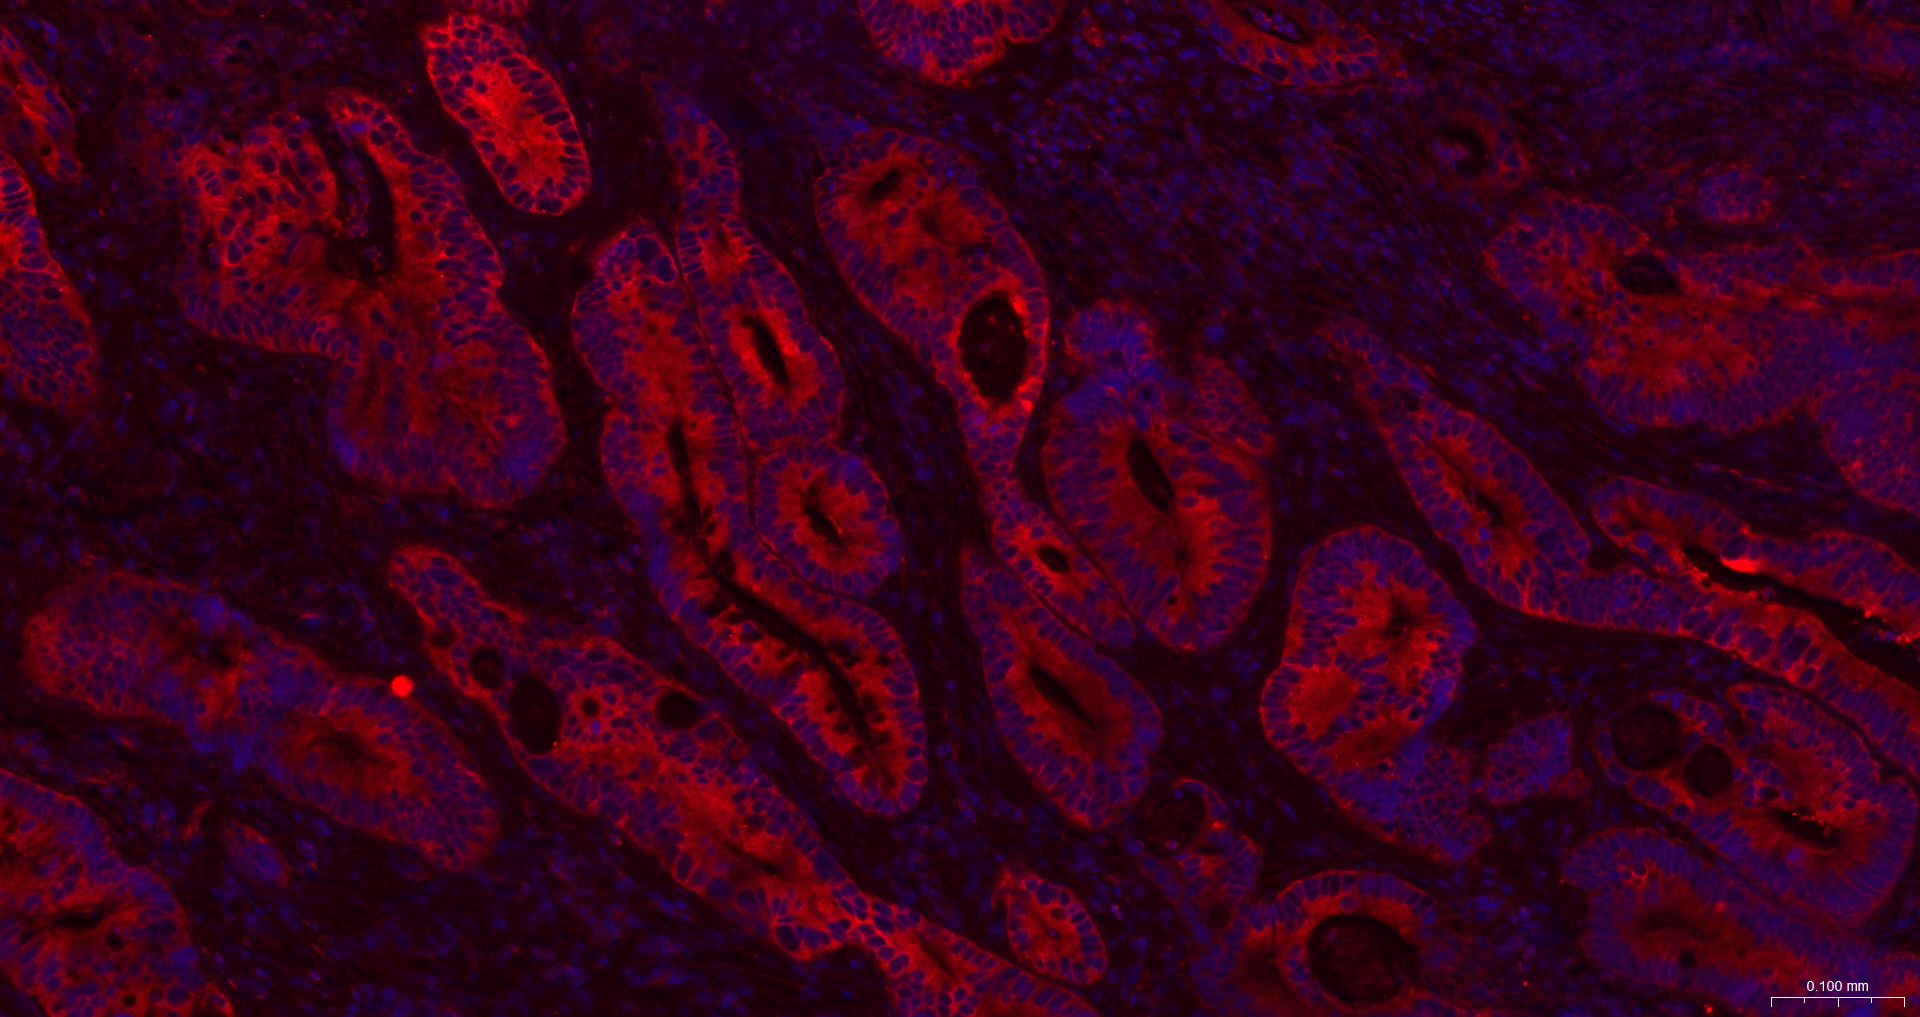

• IF(IHC-P)

IF(IHC-P) IFIHC-P1:100-500